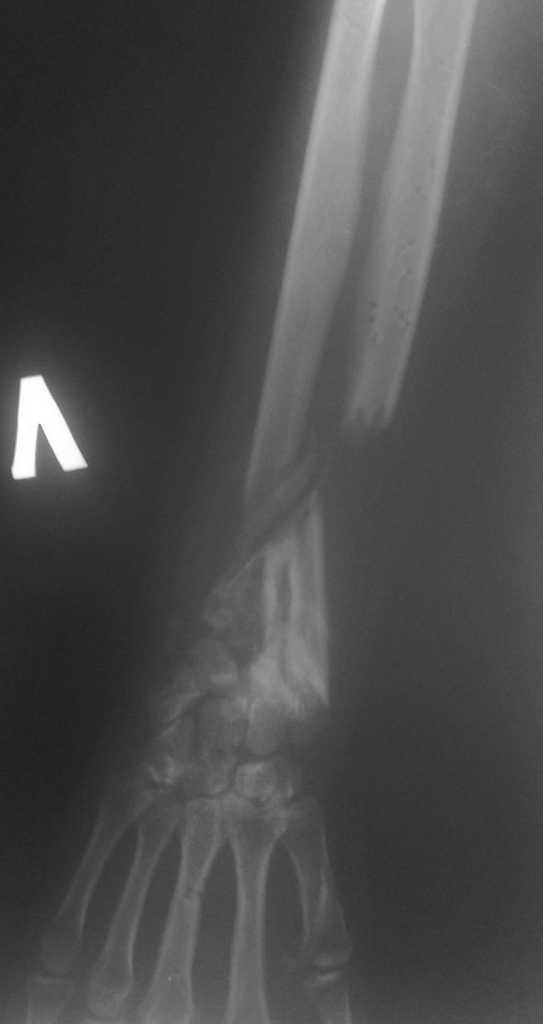

Больная Д. 30 лет плучила травму 12.07.09г, пассажир скутера -

тяжелая сочетанная травма брюшной полости и конечностей,

гемоперитониум, закрытый перелом н\3 ЛЕВОГО БЕДРА, открытый перелом

н/3 левого предплечья с дефектом обеих костей, рана голени.

С момента травмы перелом предплечья был фиксирован анкерно-спицевым

апаратом, проводилось лечение других сегментов.

В настоящий момент АВФ демонтирован, имеется следующая

рентгенологическая картина (см. приложение), имеется дефект обеих

костей и суставных поверхностей.

Имя     : прямая проекция.jpg